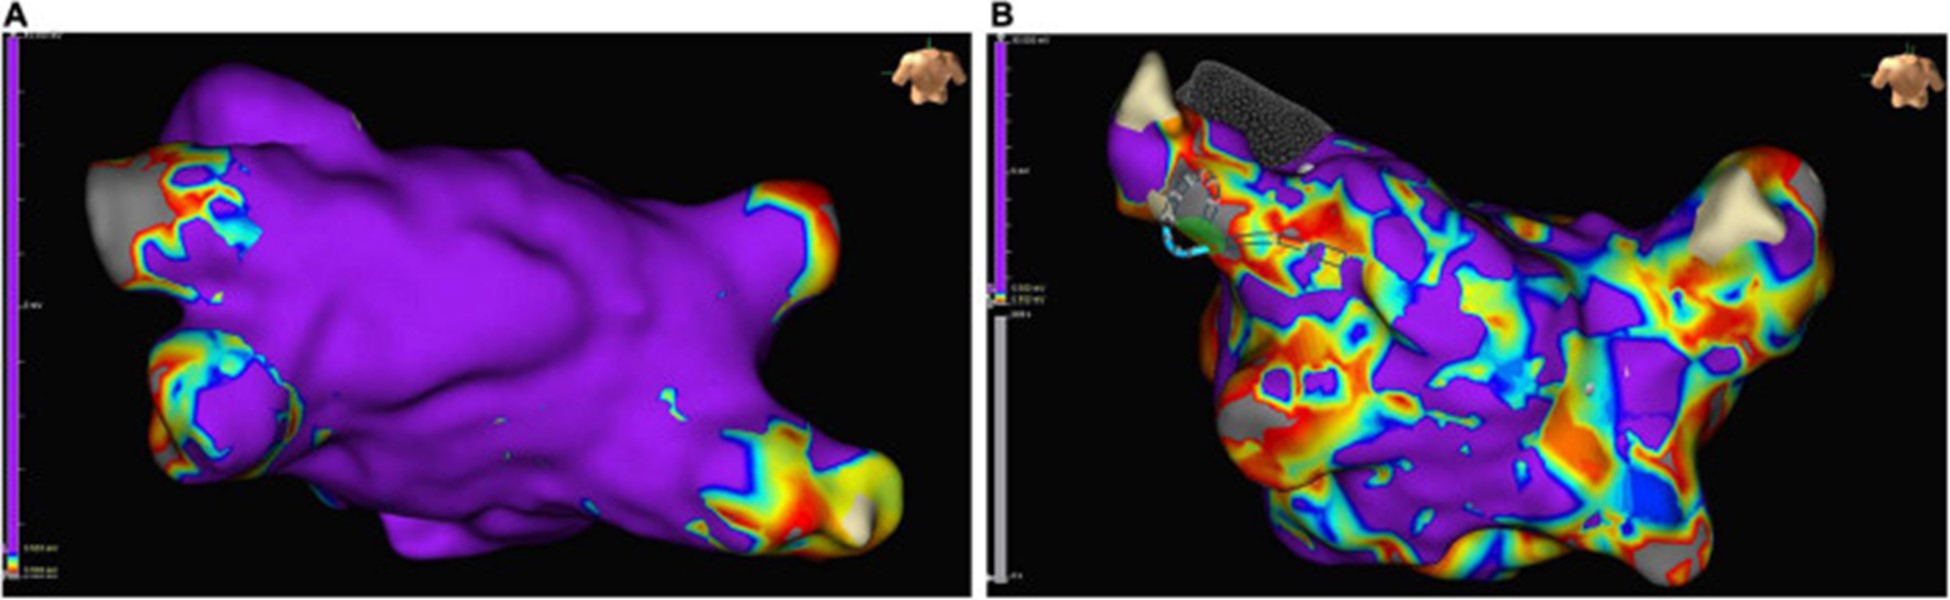

非局灶性 LA 心动过速患者在心内膜标测中出现高比例的低电压区域,为可能的左心房心肌病提供了证据 (图 6)。对纤维化左心房心肌病患者的分析显示,随着纤维化左心房心肌病的严重程度增加,严重的纤维化区域增加,最大 LA 电压降低(101)。

图 6:在接受肺静脉隔离的窦性心律患者的左心房心内膜标测中的低电压区域示例:正常传导的心房心肌呈紫色,低电压区域(定义为电感知幅度≤0.5 mV的区域)是颜色不同。(A)几乎没有低电压区域的左心房示例。(B)低电压区域 > 10% 的严重疾病左心房示例。

大多数评估电解剖标测对评估左心房心肌病的益处的研究包括接受导管消融的 AF 患者。有强有力的证据表明,AF 患者同时具有更多的低电压区域和严重的纤维化区域,反映了心房的电和结构重塑 ( 100 – 110 ) (图 6)。